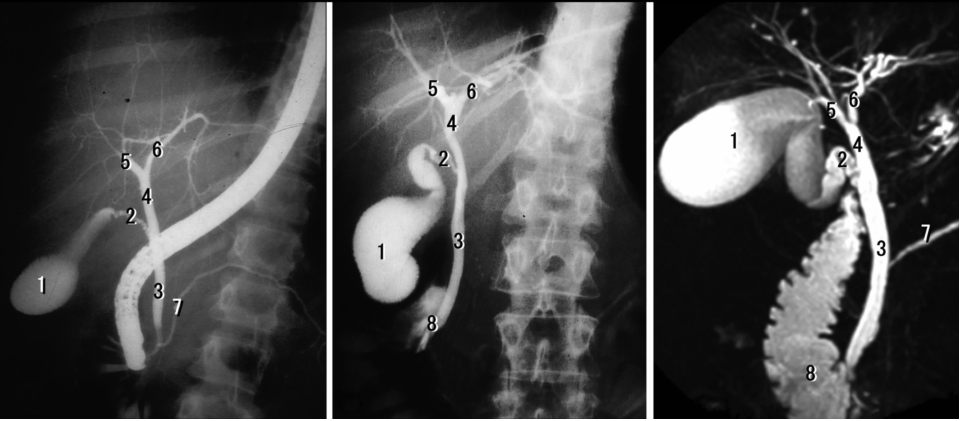

三、掌握 KUB 和 IVP 的X 线解剖。